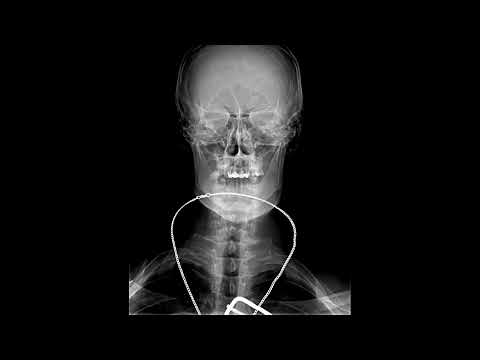

Укладка для снимка ребер

Видео-урок по позиционированию области исследования для рентгенолаборантов. Остались непонятные моменты? Задавайте свои вопросы под видео, и наши эксперты ответят на них. А может вы уже знаете, какую укладку хотите увидеть следующей? Подписывайтесь на наш канал, нажимайте "колокольчик" рассказывайте о том, что вы хотите изучать и прокачивайте свои навыки. Социальные сети Центра диагностики и телемедицины: Telegram: